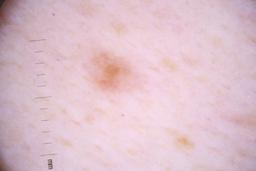

ISIC_4077341

Clinical

| Field | Value |

|---|---|

| acquisition_day | 1 |

| age_approx | 50 |

| anatom_site_1 | Trunk |

| anatom_site_2 | Anterior trunk |

| concomitant_biopsy | False |

| dermoscopic_type | contact non-polarized |

| diagnosis_1 | Benign |

| diagnosis_confirm_type | serial imaging showing no change |

| family_hx_mm | False |

| image_type | dermoscopic |

| lesion_id | IL_9238622 |

| patient_id | IP_1969685 |

| personal_hx_mm | True |

| sex | male |